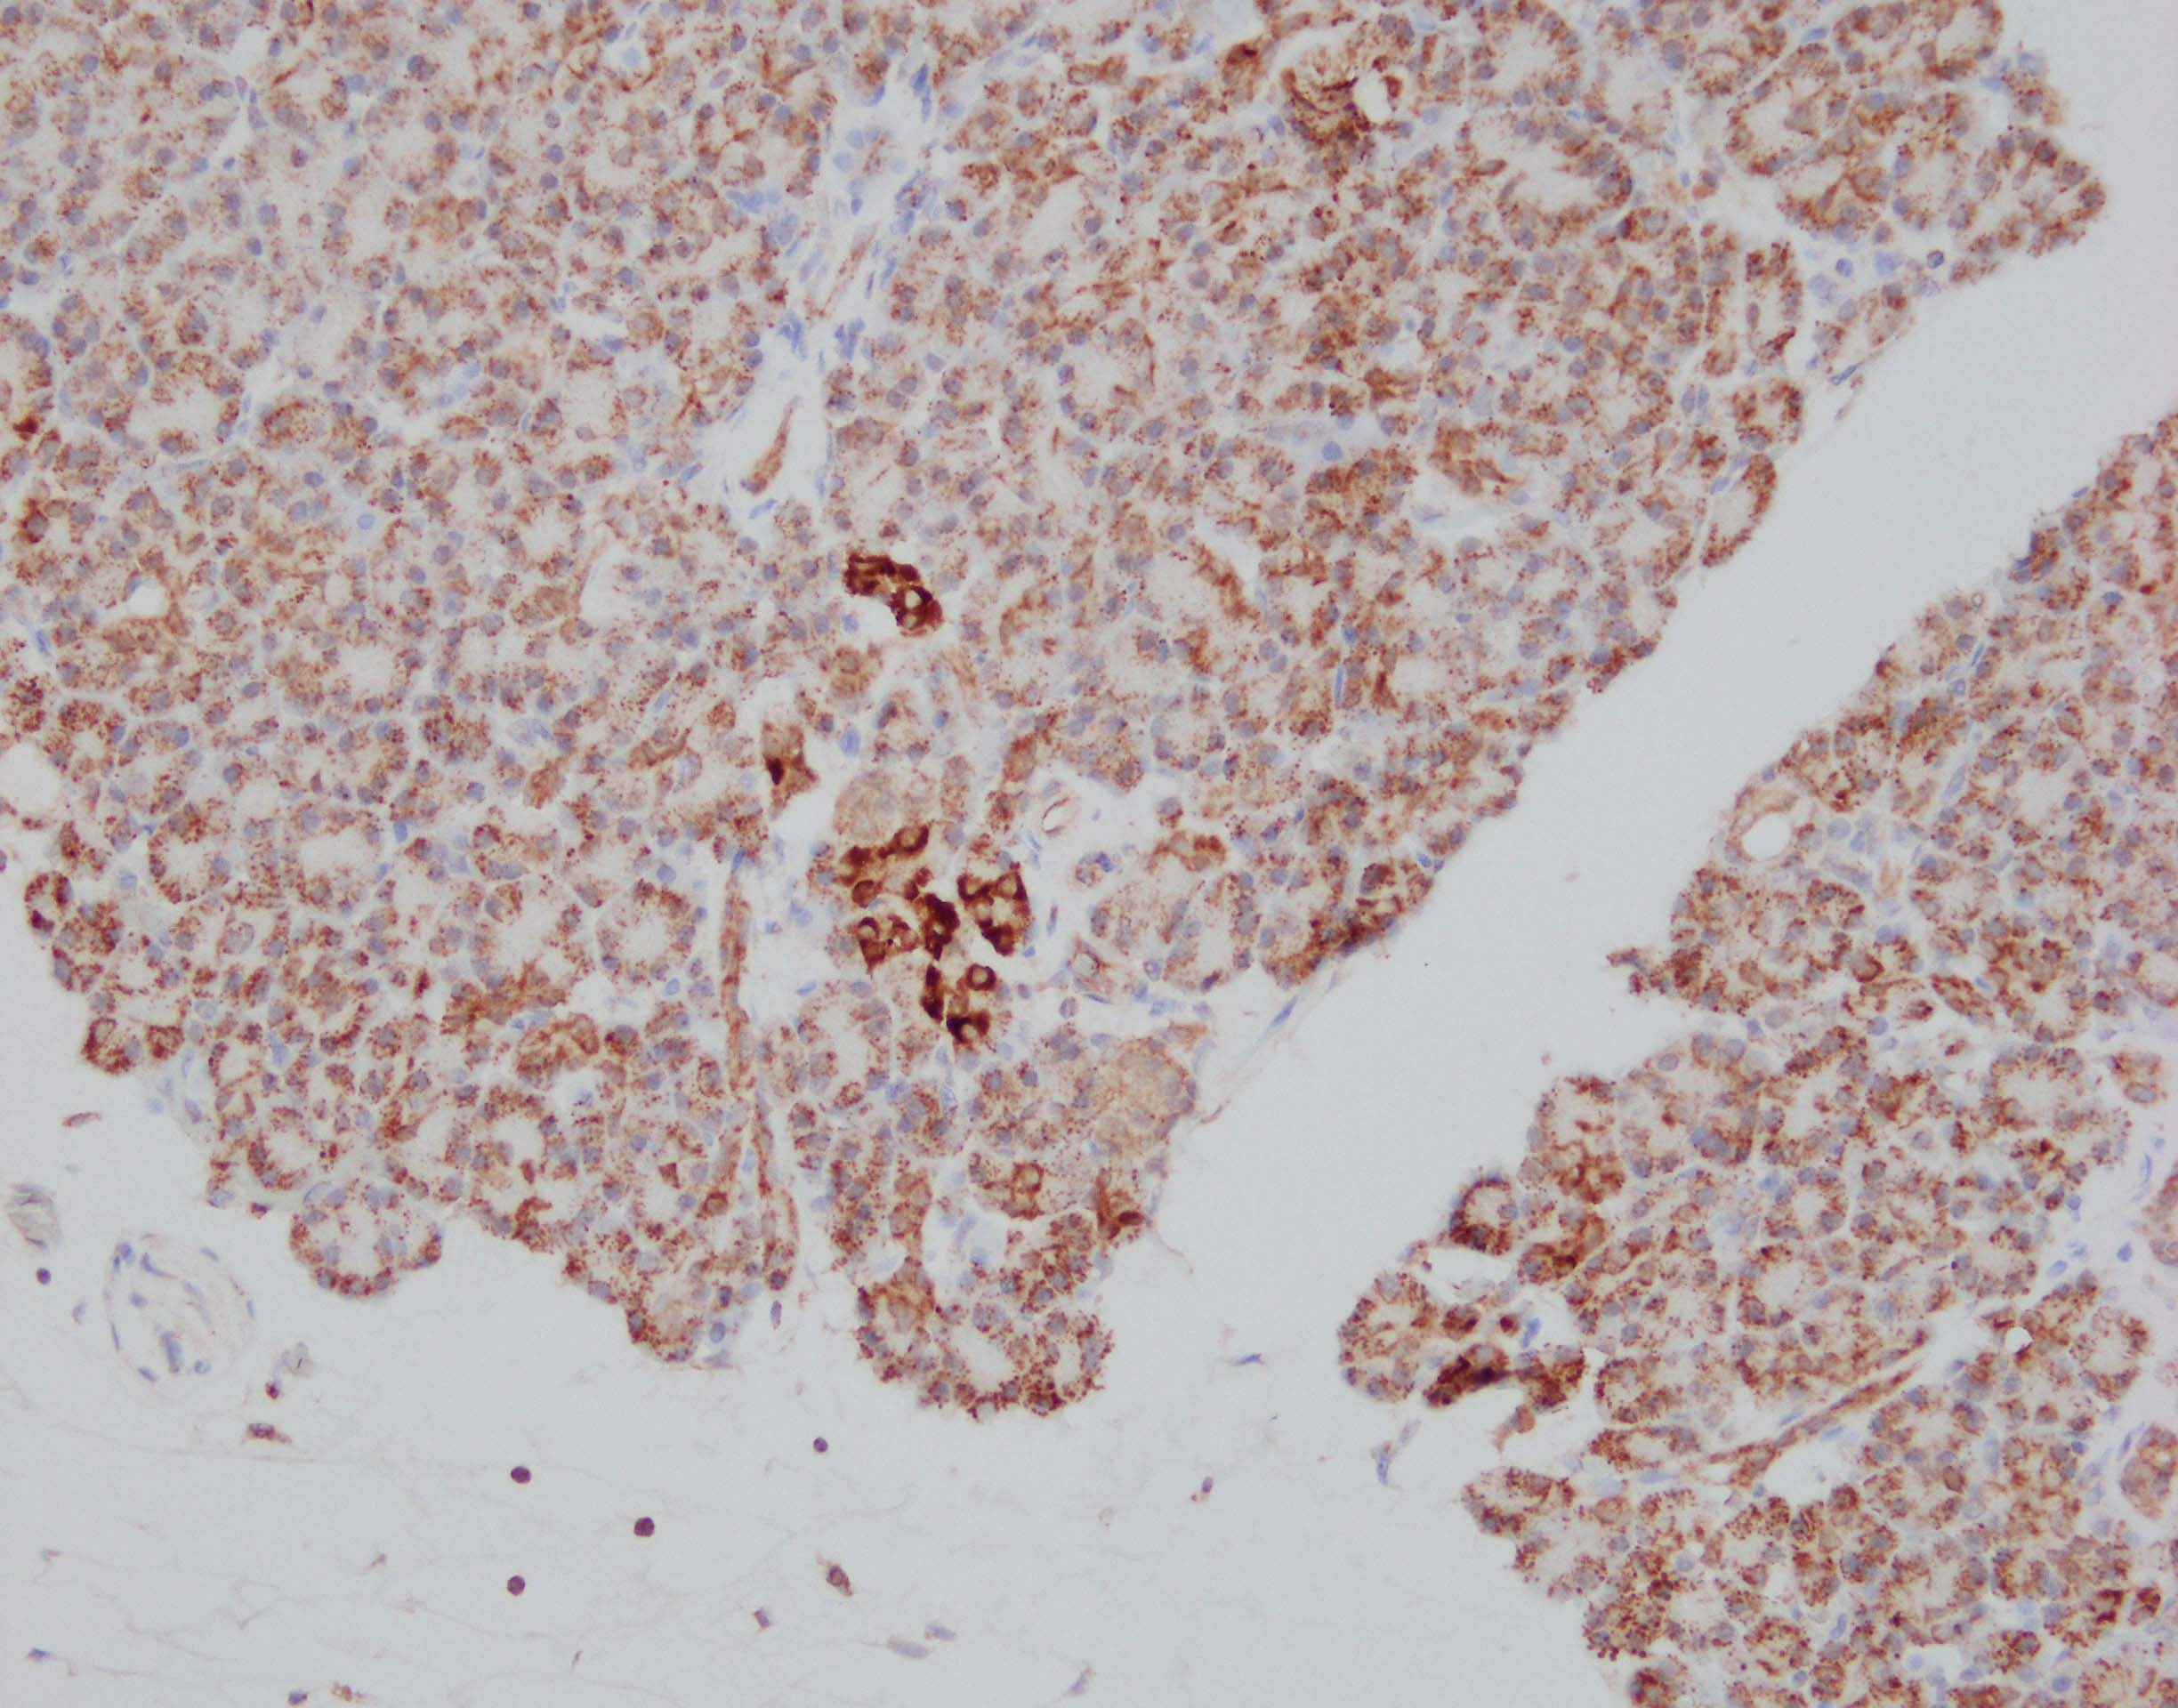

J Immunol, 2015-12-16;196(2):902-14.

Species: Human

Sample Types: Whole Tissue

Applications: IHC-P -